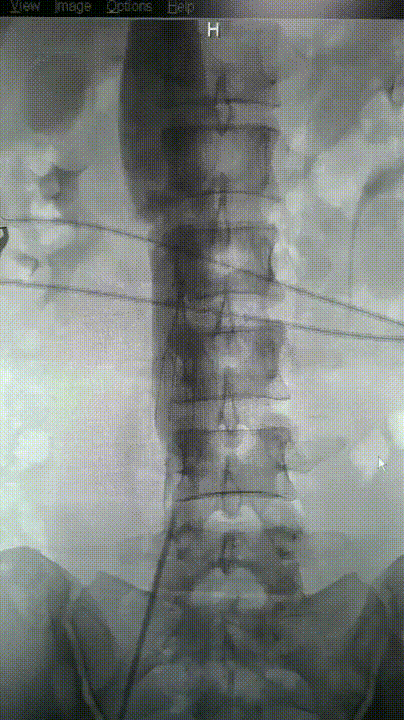

图为:尝试腔内回收滤器,滤器无法回收入鞘,下腔静脉缩窄明显

图为:腹腔镜下游离出下腔静脉